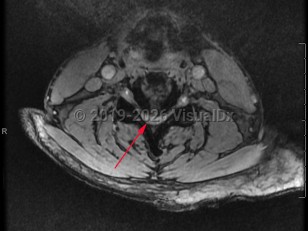

Cervical spinal stenosis is the narrowing of the spinal canal in the neck. Asymptomatic spinal stenosis may be discovered incidentally on imaging, but when it causes impingement of the spinal cord or nerve roots, symptoms can include weakness of the extremities, numbness / paresthesias, and neuropathic / radicular pain.

Narrowing of the cervical spinal canal can result in myelopathy that will result in upper motor neuron signs, such as hyperreflexia, especially in the lower extremities. Patient may experience walking difficulties or ataxia. Neck pain is common. Narrowing of the neural foramina in the cervical spine will often cause a radiculopathy. Compression of the cervical nerve roots can result in lower motor neuron signs in the upper extremities, which may result in muscle atrophy and fasciculations. Symptoms typically worsen with extension of the spine and improve with flexion.